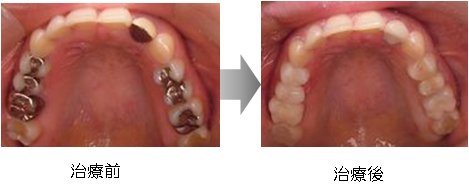

■ 症例2

30代女性。下の歯を白くしたいというご希望でした。金属を外し、白い詰め物をしました。